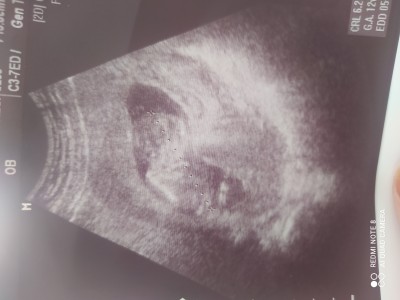

Linçlemeyin ne olur ilk gebeliğim yeni geldim doktordan ama hiç ilgilenmedi sizce ne cinsiyeti anlayan var mı :) şimdiden teşekkür ederim:))

Gebelik haftası 12+3

Erkeğe benziyor canım ensesinde çıkıntı var, Allah hayırlısını nasip etsin sen şartlama kendini daha yeniymiş